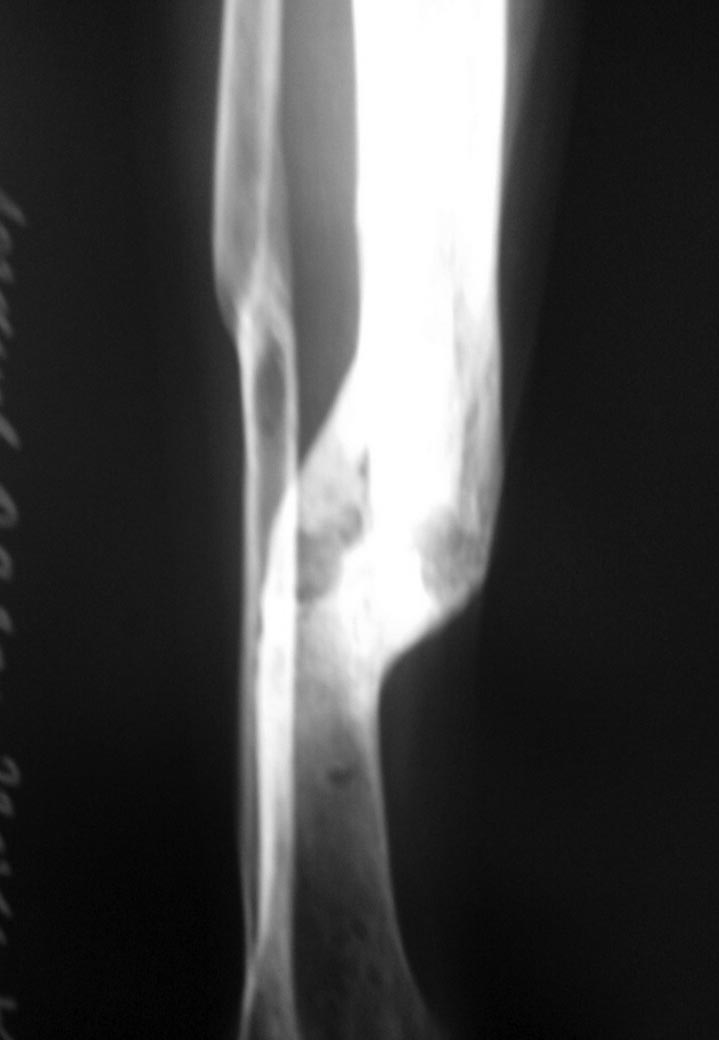

Больной в 2014 году находился на лечении в одной из Московских клиник. Диагноз: ТСТ.Перелом черепа Ушиб головного мозга. Диффузное аксональное повреждение. Длительное время находился на ИВЛ. Фрагментарный перелом плеча - консервативное лечение. Перелом голени - остеосинтез АНФ. На данный момент больной лежит в кровати. Речь понимает, отвечает односложно. Самостоятельно мог поворачиваться в пределах кровати. Поднимает нижние конечности, сгибание в коленных суставах и суставах стоп отсутствуют. При выполнении ЛФК - получен винтообразный перелом плечевой кости. У коллег прошу совета: есть мысль попробовать выполнить корригирующую остеотомию на уровне в\3 плечевой кости с последующим остеосинтезом переломов длинным гвоздем. Или выполнить остеосинтез ретроградным штифтом для дальнейшей возможности корригирующей операции, Т.к опыта таких операций нет.

Вчера несколько на эмоциях написал на форум. Более детально познакомился с пациентом. Является лежачим больным более 1.5 года, последние 3 месяца делал успехи в плане реабилитации(стал самостоятельно поворачиваться в постели, поднимает нижние конечности). Правая верхняя конечность отведение 80 гр, приведение полностью, небольшая сгибательная контрактура в локтевом суставе, сгибательная контрактура кисти и пальцев.. При выполнении ЛФК в домашних условиях 10.03.16г получен винтообразный перелом. Мягкие ткани - в подмышечной ямке кпереди по краю дельтовидной мышцы подкожно пальпируется в виде гребня костной плотности образование, кожа над ним фиксирована, а также в толще мышц избыточная костная мозоль. Первая мысль была сделать красивую рентген картинку. С учетом сниженной функциональной активности пациента, достаточно хорошей функции при таком сросшимся переломе правой верхней конечности, характером перелома(длинный винт). Выполнили сегодня остеосинтез перелома пластиной.